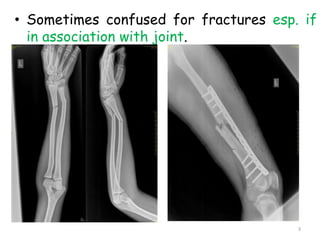

• Sometimes confused for fractures esp. if

in association with joint.